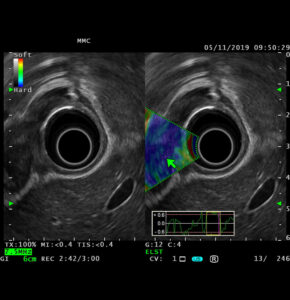

Эндоскопическая ультрасонография (ЭУС) – это высокоинформативный метод диагностики воспалительных и опухолевых заболеваний панкреато-билиарной зоны (поджелудочной железы, большого дуоденального сосочка, желчного пузыря и желчевыводящих путей) и желудочно-кишечного тракта (пищевода, желудка, двенадцатиперстной и толстой кишки), болезней печени и желчевыводящих путей, совмещающий возможности эндоскопического и ультразвукового исследований. Высокая разрешающая способность метода позволяет выявлять минимальные патологические изменения размерами до 1 мм, что превосходит возможности ультразвукового исследования (УЗИ), компьютерной томографии (КТ) и магнитно-резонансной томографии (МРТ).

ЭУС проводится при помощи специального прибора – ультразвукового эндоскопа, на дистальном конце которого расположен ультразвуковой датчик. В отличие от стандартных эндоскопических методов, ЭУС позволяет выявлять изменения не только внутренней видимой поверхности, но и всех слоев стенки органов желудочно-кишечного тракта и анатомических структур за ее пределами. Высокочастотные звуковые волны создают детальные изображения пищеварительного тракта и окружающих органов и тканей, включая поджелудочную железу, желчный пузырь, печень и лимфатические узлы.

Эндоскопическое ультразвуковое исследование работает аналогично УЗИ брюшной полости, за исключением того, что источник звуковых волн находится внутри тела. Когда высокочастотные звуковые волны распространяются от эхоэндоскопа, они попадают на ткани различной плотности и отражаются обратно. Например, эндоскопическое ультразвуковое исследование может выявить очертания опухоли или кисты, которые затем компьютер обрабатывает и отображает на экране в виде более светлых и темных участков.

Поскольку звуковым волнам не нужно проходить через кожу и мышцы, чтобы достичь внутренних органов, ЭУС обеспечивает лучший обзор желудочно-кишечного тракта и близлежащих органов, чем УЗИ брюшной полости.